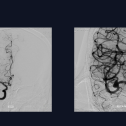

【“佟”话脑血运】佟志勇教授:大脑中动脉M1中段解离性动脉瘤的外科治疗策略

佟志勇

前天14:14